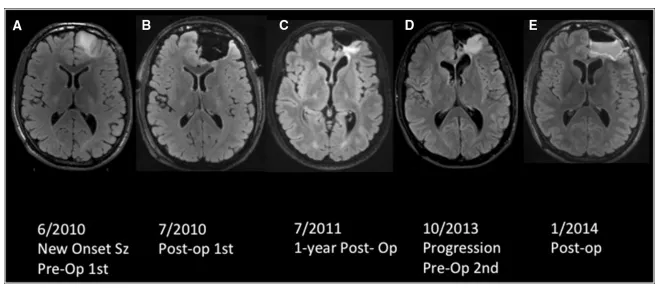

双胞胎兄弟先后确诊胶质瘤的病例引发对疾病遗传性的关注。首例患者为17岁男性,足球运动时突发癫痫就诊,神经系统检查未见异常。MRI影像显示左侧额叶前部存在非强化占位病变。首次手术实现次全切除,病理确诊为WHO 2级少突胶质细胞瘤,伴有1p/19q共缺失。

首例患者完成替莫唑胺12个月周期治疗后,MRI显示T2高信号区域扩大,提示肿瘤进展。继续追加12个周期替莫唑胺治疗后,影像学出现对比增强区域,表明肿瘤发生间变转化。二次手术病理确诊为WHO 3级间变性少突胶质细胞瘤,遗传学检测显示1p19q共缺失、PTEN野生型、无EGFR扩增。术后接受放疗联合CCNU方案化疗,目前病情稳定。

其兄长在次全切除术后3年随访中,MRI显示肿瘤进展接受二次手术,病理证实转化为WHO 3级间变性少突胶质细胞瘤,后续计划接受放化疗联合治疗方案。